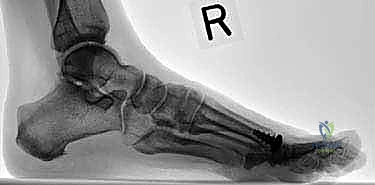

- التصوير الإشعاعي (X-rays):

وهو الأداة الذهبية لتشخيص تيبس إبهام القدم. تُظهر الأشعة السينية بوضوح: - تضيق المسافة بين العظام (دليل على تآكل الغضروف).

- وجود النتوءات العظمية (Bone Spurs).

- أي تكيسات عظمية أو تشوهات في شكل المفصل.